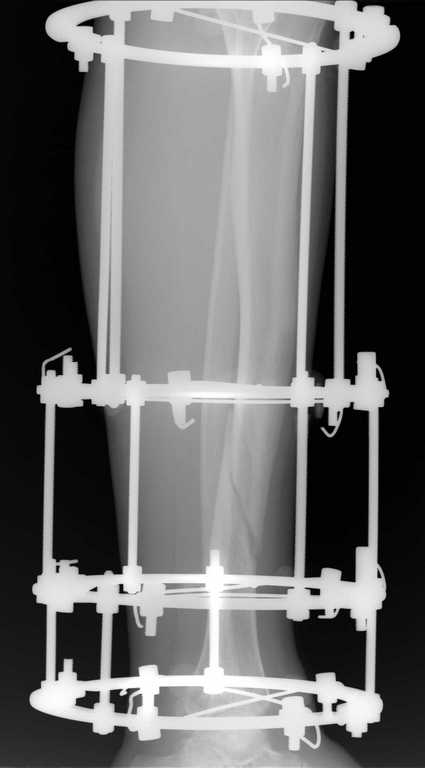

Уважаемые коллеги, доброго времени суток. Пациент 40 лет, получил травму в марте 2010 г, на

следующий день прооперирован ЧКДО по Илизарову. последние снимки от 15.07.10. Пациент

передвигается с полной нагрузкой на оперированую конечность, болей нет. Вопросы: 1.

снимать аппарат? 2. если снять и появиться подвижность, что делать? 3. возможно ли в такой

"изогнутый" канал большеберцовой кости установить штифт, если да, то какие могут быть

сюрпризы? Заранее спасибо.

Имя     : голень боковая.jpg

Имя     : голень прямо.jpg